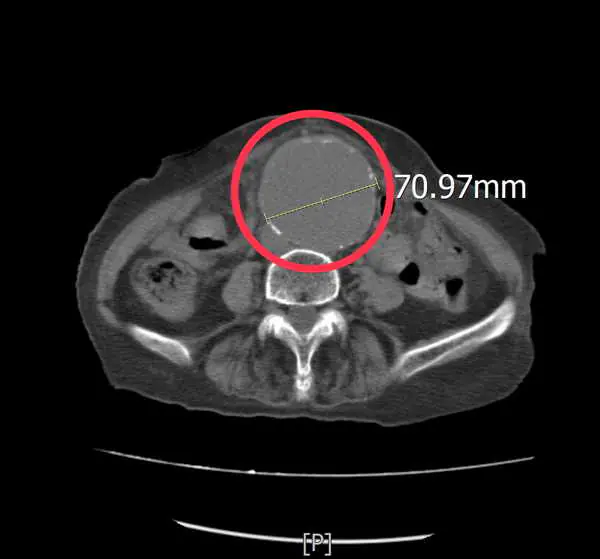

透過即時影像檢查,孫秀正醫師發現患者的腹主動脈明顯擴張,直徑已超過7公分,高度懷疑為腹主動脈瘤,進一步安排電腦斷層檢查確認診斷,結果顯示確實為大型腹主動脈瘤。

孫秀正醫師表示,腹主動脈瘤,是腹部主動脈血管壁因退化或動脈硬化而逐漸擴張,當血管直徑持續增大,血管壁會變得脆弱,一旦發生破裂,可能在短時間內造成大量內出血,死亡率極高。當腹主動脈瘤直徑大於5至5.5公分時,破裂風險即明顯增加,而該患者的腹主動脈瘤已超過7公分,屬於極高風險狀態,因此必須儘速處理。

圖二:紅圓圈為病兆處。